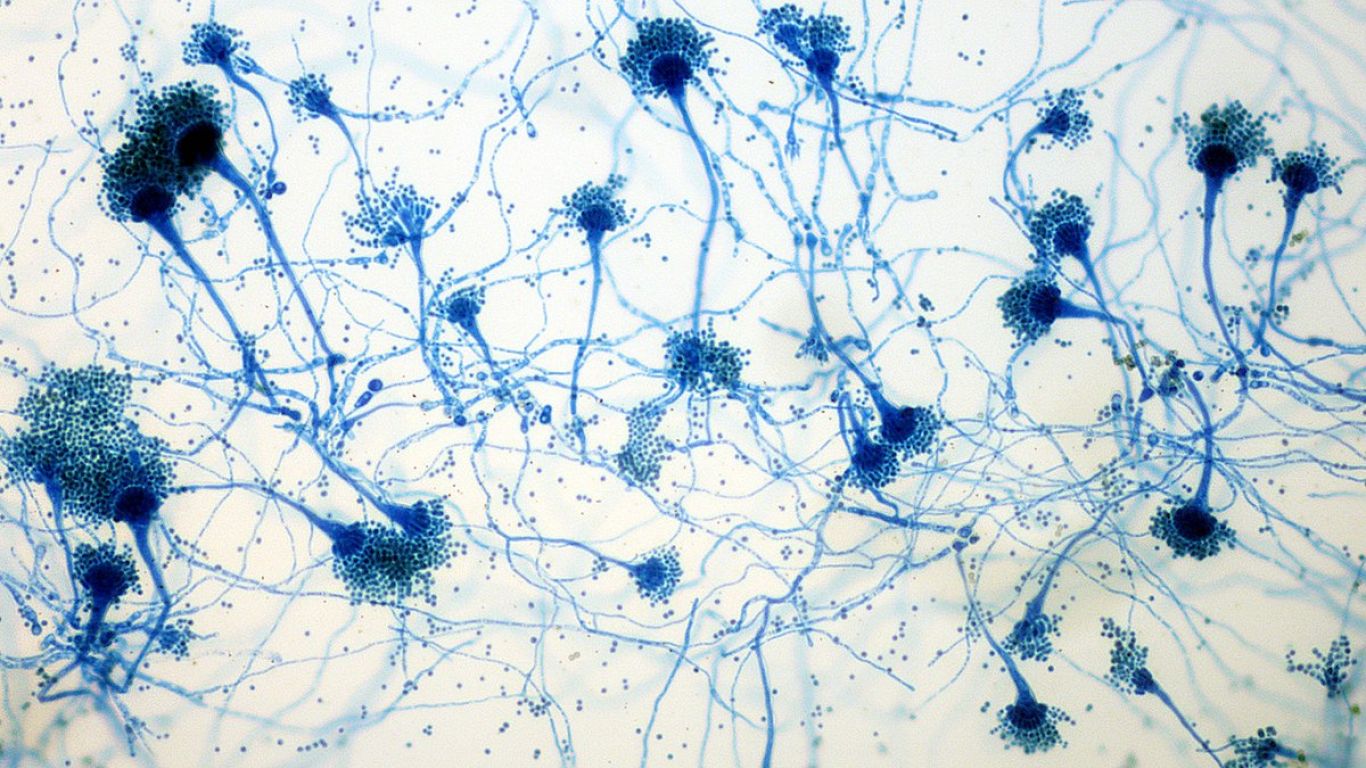

İngiltere’de koronavirüsün mutasyona uğramış hali tespit edildi. Göğüs Hastalıkları Uzmanı Prof. Dr. Şevket Özkaya, mutasyona uğramış virüs hakkında açıklamalarda bulunarak koronavirüsü ağır geçirmiş bir evli çiftin akciğerleri üzerinden örnekler verdi.

İncelediği akciğerlerin ve verdiği vaka örneğinde direkt temasın, bulaşıcılığı ve hastalığı çok hızlı ilerlettiğini gösterdiğine dikkat çeken Prof. Dr. Şevket Özkaya, “Örnek vermek gerekirse, bir karı-kocanın çocuklarının ikisi de pozitif olan ama genç oldukları için akciğerleri tutulmamış ama genç-taşıyıcı olduğu için anne ve babalarına bulaştıran aile içindeki gözlemlenen vakayı sizle paylaşacağım. Bu kadın hastamızda, kızından aldığı virüs nedeniyle oluşan çok hafif pulmoner akciğer tutulumu şikâyeti birkaç gün içerisinde hızla ilerliyor ve yaygın solunum yetmezliği ortaya çıkıyor. Bu vaka, direkt temasın çok hızlı bulaşıcılığını ve hastalığın çok hızlı ilerlediğini gösteriyor.

Hastamızın eşine baktığımızda da yine kızından bulaşan virüsle akciğerinde hafif bir tutulma olduktan sonra çok hızlı bir şekilde ilerleyip hastaneye yatacak düzeyde bir nefes darlığı ortaya çıktığını gördük. Halkın mutasyona uğrayan korona virüsüyle ilgili bilmesi gereken iki nokta var. Birincisi mutasyonlu virüs çok hızlı şekilde bulaşabilir, çünkü bulaştırıcılığı çok fazla. İkincisi de tedaviye rağmen düzelme görülemeyebilir ama bu mutasyon olduğunu göstermez” diye konuştu.